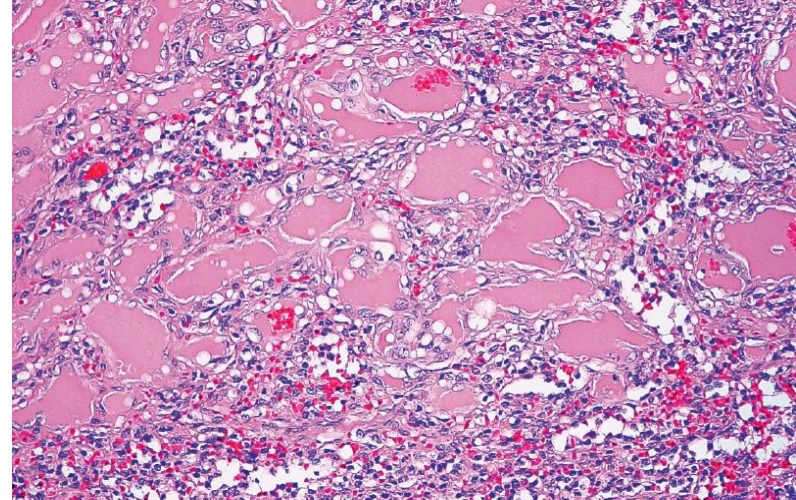

What is the morphology of lymphangiomas? Who do they occur in?

subcapsular region of the spleen; multicystic; lumina contain proteinaceous material, not RBCs; endothelium may form small papillary projections

most cases in children